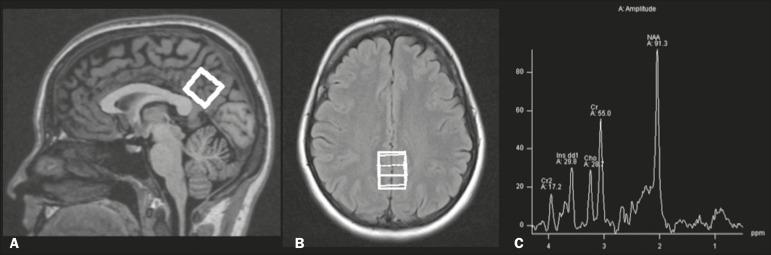

We aimed to evaluate whether human immunodeficiency virus (HIV)-positive patients with and without clinically significant memory deficits and healthy control participants differ on in vivo hydrogen-1 magnetic resonance spectroscopy (H-MRS) in the posterior cingulate gyri.

MATERIALS AND METHODS

In total, 21 HIV-positive patients with memory deficit (HIV+wMD) were compared with 15 HIV-positive patients without memory deficit (HIV+wOMD) and 22 sex-, age-, and education-matched control participants. Memory impairments were classified based on the participants' performance on the Rey Auditory Verbal Learning Test. Short echo time (30 ms), single-voxel H-MRS was performed using a 1.5-T magnetic resonance scanner.

The HIV+wMD and HIV+wOMD groups had higher choline/creatine ratio in the posterior cingulate gyri than the control group. There were no significant metabolite ratio differences between the HIV+wMD and HIV+wOMD groups.

HIV-positive patients with and without memory deficits had significantly higher choline/creatine ratios than controls in the posterior cingulate gyri, which may reflect cerebral inflammation, altered cell membrane metabolism, microgliosis, and/or astrocytosis.

我们旨在评估有和没有临床显著记忆缺陷的人类免疫缺陷病毒(HIV)阳性患者以及健康对照参与者在后扣带回的体内氢-1磁共振波谱(H-MRS)是否存在差异。

材料与方法

总共将21名有记忆缺陷的HIV阳性患者(HIV+wMD)与15名无记忆缺陷的HIV阳性患者(HIV+wOMD)以及22名性别、年龄和教育程度匹配的对照参与者进行比较。根据参与者在雷伊听觉词语学习测验中的表现对记忆损害进行分类。使用1.5-T磁共振扫描仪进行短回波时间(30 ms)的单体素H-MRS。

HIV+wMD组和HIV+wOMD组后扣带回中的胆碱/肌酸比值高于对照组。HIV+wMD组和HIV+wOMD组之间的代谢物比值无显著差异。

有和没有记忆缺陷的HIV阳性患者后扣带回中的胆碱/肌酸比值均显著高于对照组,这可能反映了脑部炎症、细胞膜代谢改变、小胶质细胞增生和/或星形细胞增生。